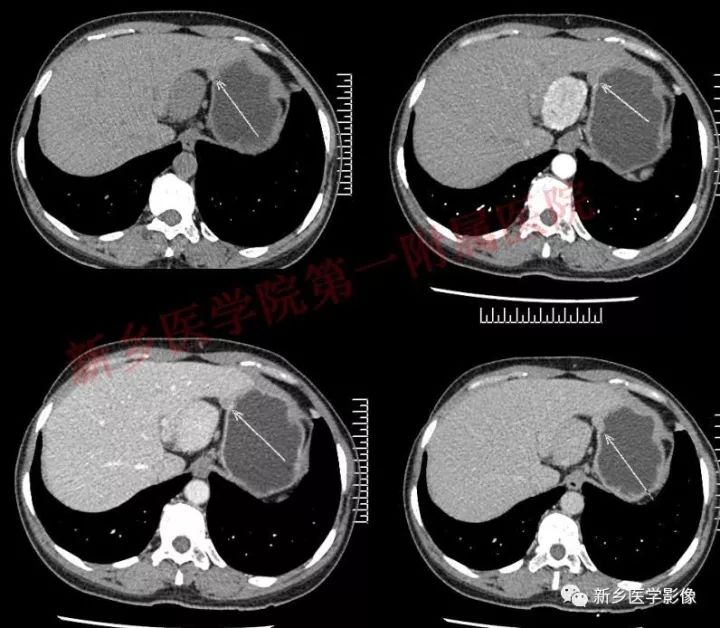

患者,女,47岁,发现“腹部肿瘤”半年,无明显不适。

肝胃间胰腺前上方见类圆形肿块,边界较清,大小约8.2cm×4.6cm×5.9cm,密度欠均匀,内见点状钙化,增强呈不均匀明显强化,内见片状低密度灶无强化区,其下部与相邻胰腺分界不清,周围见粗大回流血管影回流至门静脉,病变左侧及腹膜后、胃壁小弯侧见数个卵圆形稍大淋巴结及结节影,部分呈环形强化。

石蜡:(腹腔肿物、腹腔动脉旁、胰腺上缘)Castleman病(巨淋巴结增生),玻璃样变血管型。

免疫组化结果显示:Bcl-2(生发中心-),CD10(-),CD21(生发中心 ),CD3( ),CD43( ),CD5( ),CyclinD1(-),Ki-67( 5~10%),CD20( )。